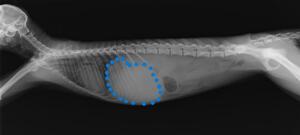

↓2022年のレントゲン写真(青い点が肝臓)。